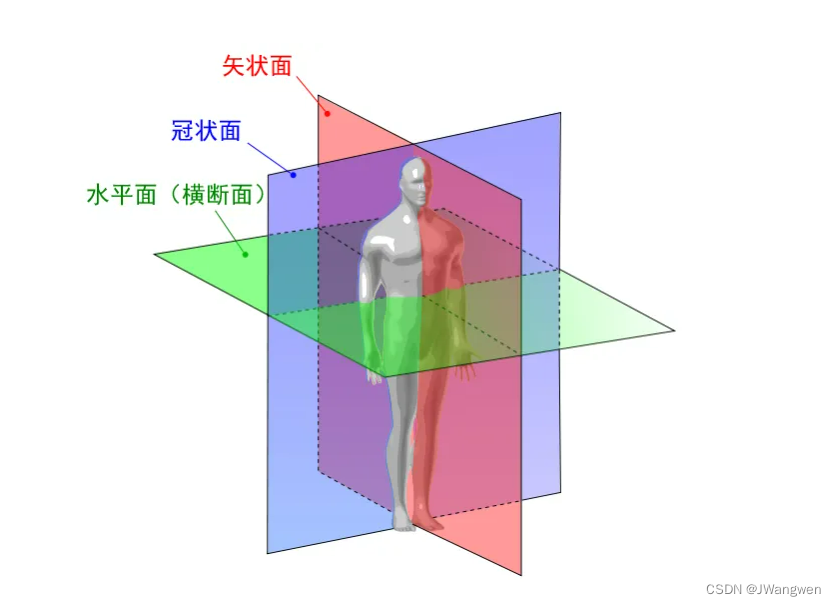

nii图像为三维图像,进行切片后分别表示

矢量面Median sagittal section (人体从前向后切开)

冠状面coronal section (人体沿左向右切开)

水平面Transverse section